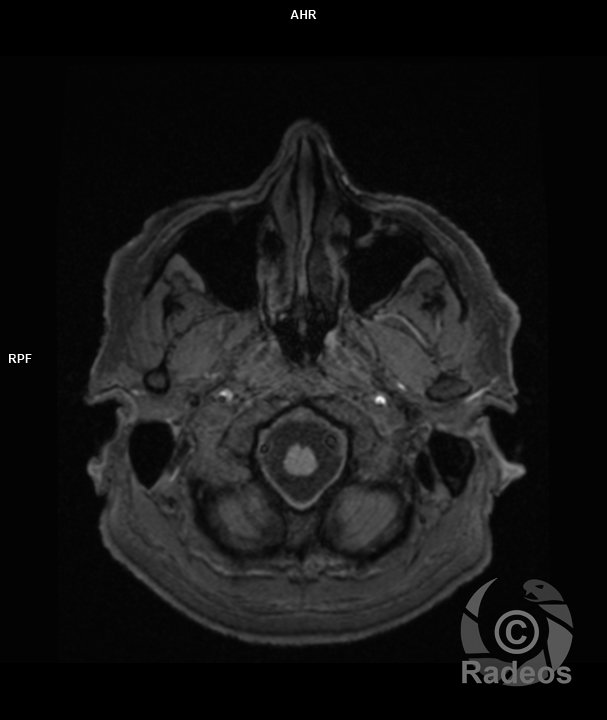

Trouvez le diagnostic du cas du jour